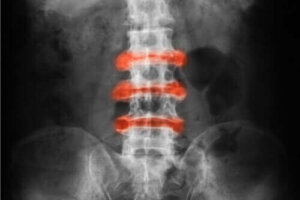

Ankyloserende spondylitis er inflammatorisk gigt, der især forekommer i ryg- og bækkenleddene. Akutte lidelser og stivhed har en tendens til at blive bedre med fysisk aktivitet, og inaktivitet kan forværre sygdommen.